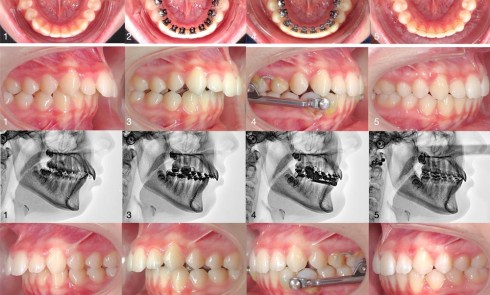

Définition et prévalence La succion est une activité instinctive et réflexe chez le nouveau-né, essentielle à l’alimentation et à la...